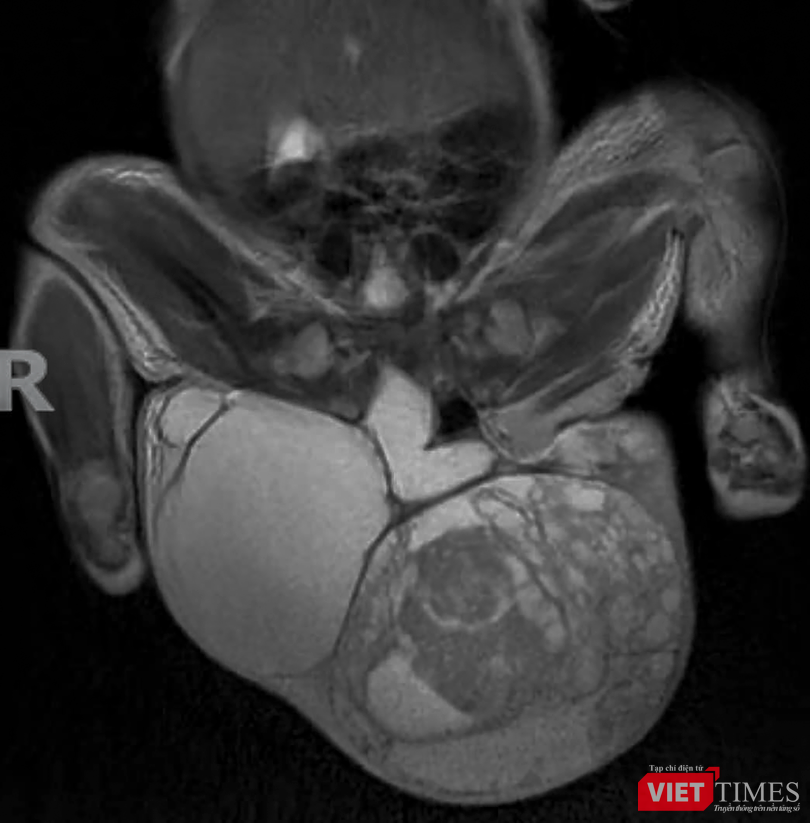

ThS.BSCK2. Nguyễn Phi Phong – Khoa Ngoại nhi, Bệnh viện Phụ sản – Nhi Đà Nẵng - cho biết, trẻ là con của sản phụ ở Kon Tum. Khối u được phát hiện lúc thai 18 tuổi và theo dõi thai tại Bệnh viện Phụ sản – Nhi Đà Nẵng. Khi đủ tháng, trẻ được sinh mổ, chào đời với cân nặng 3,2kg. Tuy nhiên sau sinh, ở vùng cụt của trẻ có khối u lớn hơn 15cm và nặng hơn 1,2kg.

Sau khi chẩn đoán và hội chẩn thống nhất phương án, các bác sĩ Khoa Ngoại nhi đã phối hợp với Khoa Nhi sơ sinh và Khoa Gây mê tiến hành phẫu thuật cắt khối u. Ca phẫu thuật kéo dài hơn 2 tiếng, khối u đã được cắt bỏ thành công. Kết quả giải phẫu khối u cho thấy là hỗn hợp dịch, xương, lông tóc và mô mềm.

“Khối u có nguồn gốc từ tế bào phôi thai. Mức độ ác tính tùy thuộc vào độ trưởng thành của khối u và độ tuổi mổ. Tỷ lệ gặp rất hy hữu từ 1/35.000 - 1/40.000 ca mắc. Hiện trẻ đang được tiếp tục hồi sức và điều trị sau mổ và chờ kết quả sinh thiết khối u để đánh giá và tiên lượng cuộc sống của trẻ sau mổ”- ThS.BSCK2. Nguyễn Phi Phong cho hay.

Phim X-quang khối u (Ảnh BVCC)